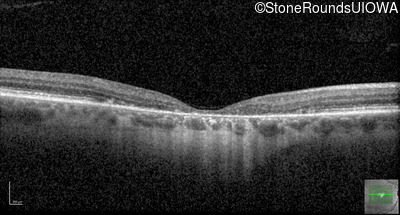

Optical Coherence Tomography - Right - 20/200 +2

Exemplar / OCT Stack